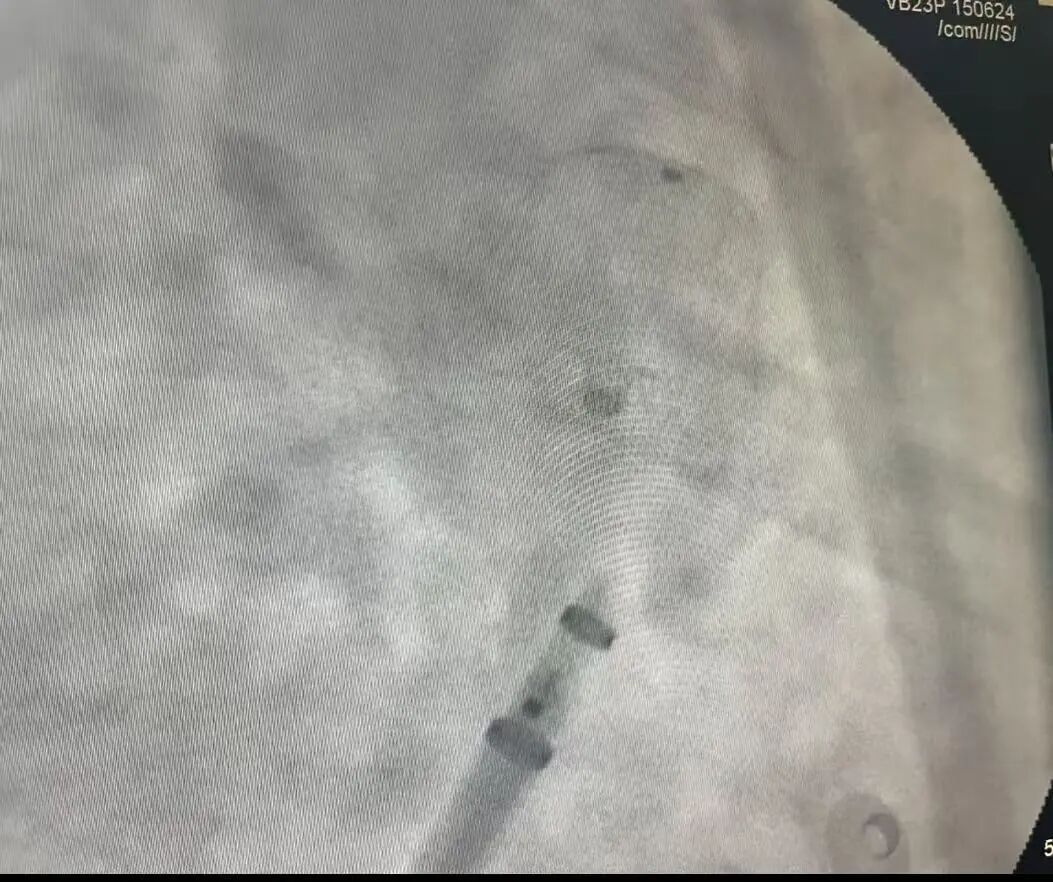

近日,我院心血管内科起搏电生理团队在王俊莉主任的带领下,凭借精湛医术及团队默契协作,成功完成我院首例独立“一站式”手术,即心脏射频消融术+左心耳封堵术。这一高难度联合手术的独立开展,标志着我院心血管内科在心律失常综合治疗领域达到了区域内先进水平,为房颤患者解除心源性卒中隐患,撑起了一把远离卒中的“保护伞”。

病例回顾:接受手术的是一位62岁的男性患者,既往有高血压及脑梗死病史,且有一侧肢体活动障碍,入院前3个月无明显诱因出现头晕、气短症状,偶有心悸,持续数分钟,休息后症状缓解,为求明确诊治,来我院门诊,发现心律失常,心房颤动,收入我科进一步治疗。王俊莉主任通过评估,评定患者有较高的卒中风险,且患者口服抗凝药物后出现较重的牙龈出血,经充分讨论和与其家属沟通后,决定为其实施房颤射频消融+左心耳封堵“一站式”手术,希望用一次介入手术,尽量减少患者的痛苦及风险。在天津医科大学总医院心血管内科房颤中心医疗主任蔡衡的指导与帮助下,手术顺利开展。术后患者恢复情况良好,已康复出院。

心血管内科王俊莉主任介绍:房颤射频消融+左心耳封堵“一站式”手术具有很大的挑战性,对手术医生的经验和操作要求都非常高,此次手术的成功完成切实提高了我院房颤综合治疗技术水平,也为广大心血管病患者特别是心房颤动患者提供更加优质的医疗技术服务!